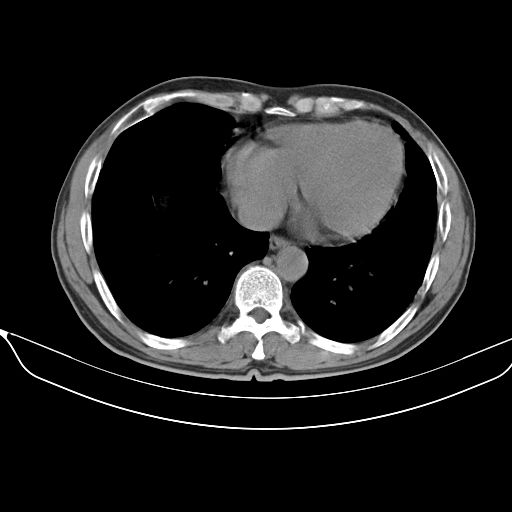

以下是引用shuiyuan在2010-3-1 10:45:00的发言:[br]考虑左肺上叶中心型肺癌伴阻塞型炎症,邻近胸膜受侵。

以下是引用心路寻觅在2010-3-1 10:23:00的发言:[br]1、考虑左肺上叶周围型肺癌[br]2、右上肺陈旧性病灶。[br][br][本贴已被 心路寻觅 于 2010-3-1 10:40:18 修改过]